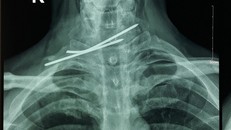

Hình ảnh X-quang cho thấy cây kim đâm xuyên thực quản và khí quản bệnh nhân - Ảnh: Sức khỏe Đời sống

Người đàn ông bị đinh y tế đâm xuyên thực quản, khí quản

(Ngày Nay) - Được phẫu thuật kết hợp xương đòn cách đây 2 năm nhưng do tái khám quá muộn, một người đàn ông bị đinh kirschner đâm xuyên thực quản và khí quản.